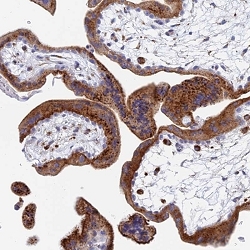

Supportive validation

- Submitted by

- Abnova Corporation (provider)

- Main image

- Experimental details

- Immunohistochemical staining of human placenta with SPNS1 polyclonal antibody ( Cat # PAB28037 ) shows strong cytoplasmic positivity in trophoblastic cells at 1:50 - 1:200 dilution.

- Validation comment

- Immunohistochemistry (Formalin/PFA-fixed paraffin-embedded sections)